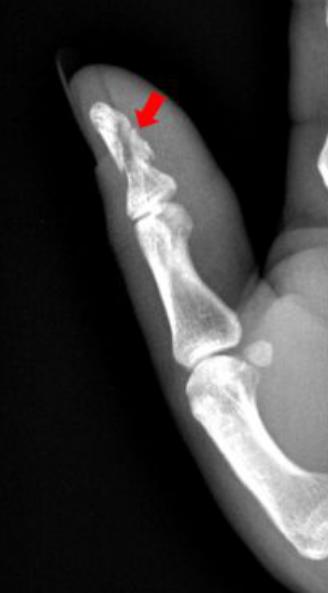

1、患者拇指被车门挤压,拍片如下:

右手拇指远节指骨甲粗隆游离骨碎片影

2、患者拇指被锤子砸伤,拍片如下:

右手拇指末节指骨见数条骨折线,骨折端对位对线尚可,右手拇指末节指骨粉碎性骨折。